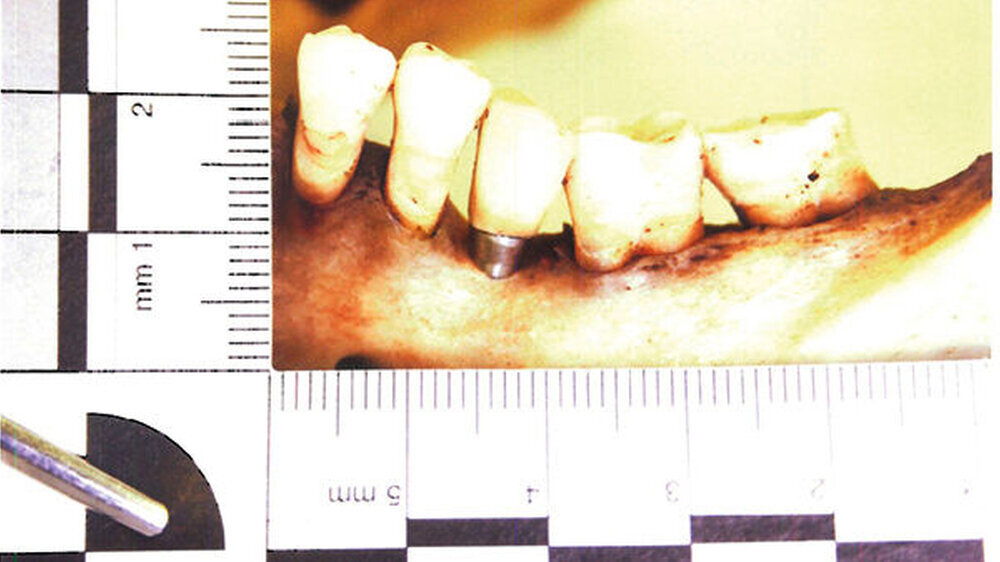

Zahnstatus:Aus dem Zahnstatus ersichtlich ist, dass es sich um hochwertige zahntechnische Arbeiten handelt, die auf eine mögliche privatkassenärztliche Versorgung schließen lassen. Der forensisch-odontologische Gutachter vermutet, dass alle Arbeiten durch denselben Zahnarzt gemacht wurden.

Neu:Inzwischen hat sich ergeben, dass es sich mit sehr hoher Wahrscheinlichkeit um XIFE-Implantate der Firma Densply Implants handelt.